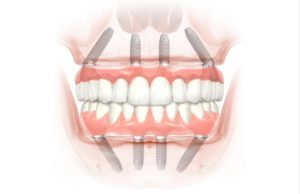

All-on-Four es la solución para los pacientes que desean una restauración fija de sus dientes en un día. La revolucionaria técnica All-on-Four permite a los pacientes recibir un puente fijo (no removible) completo en tan sólo 4 implantes dentales. ¡Todo el mismo día!

Incluso los pacientes que se les ha dicho que no son candidatos de implantes dentales, debido a la pérdida de hueso, son ahora capaces de restaurar sus sonrisas mediante la utilización de esta técnica.

Prácticamente todos los pacientes con dentadura postiza, aquellos con fracasos en anteriores tratamientos, e incluso aquellos con pérdida ósea severa por enfermedad periodontal ahora tienen la opción de recuperar su sonrisa.